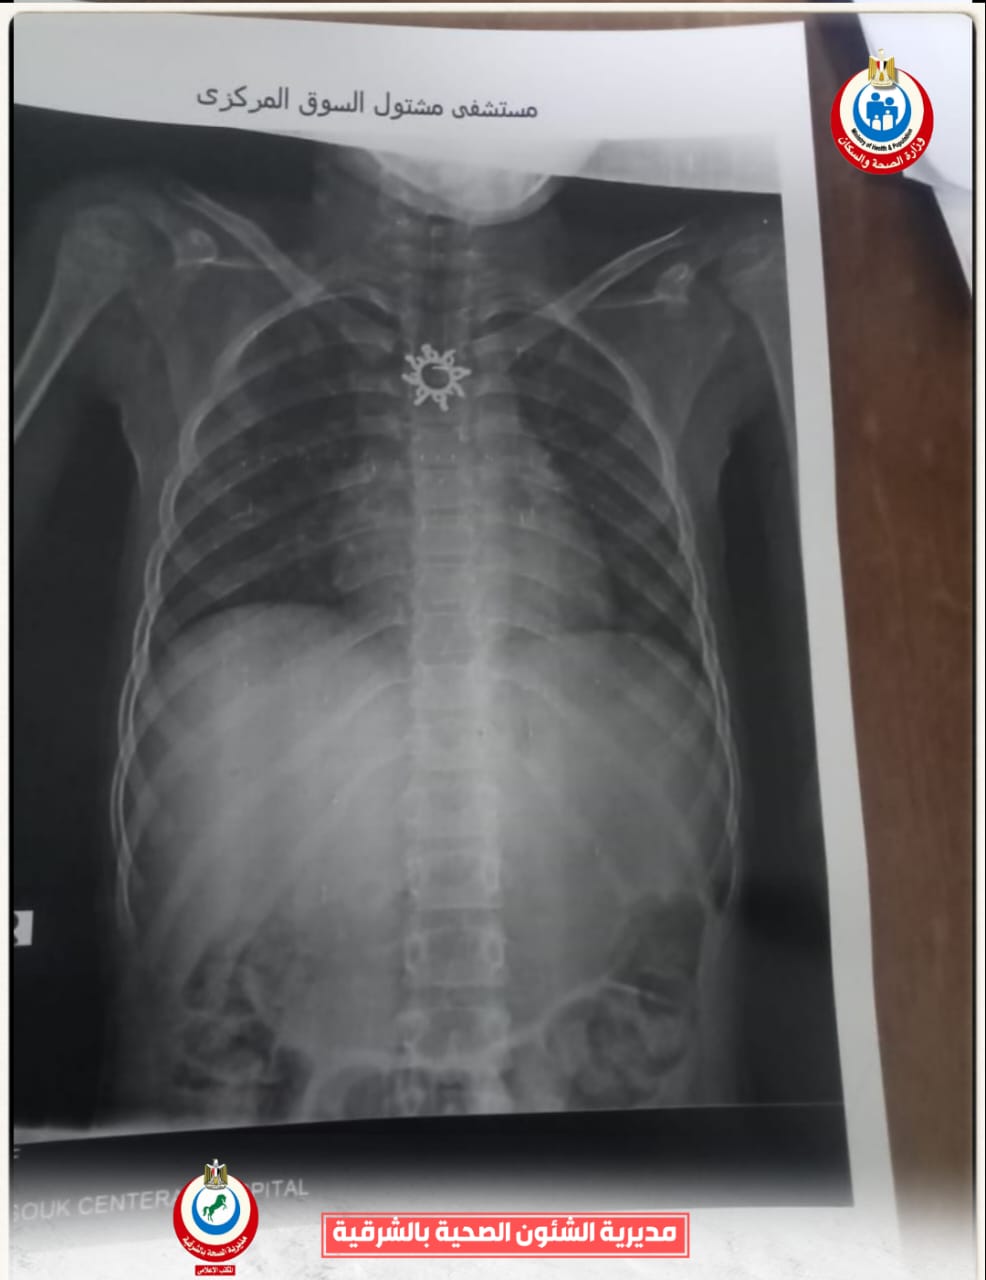

وأوضح الدكتور أحمد البيلي وكيل وزارة الصحة أن قسم المناظير بمستشفى أبو كبير شهد نجاح مميز في إنقاذ الطفلة التي تبلغ من العمر ٥ سنوات، وقامت بابتلاع سلسلة معدنية حادة ومدببة وأطرافها قادرة على إحداث جروح أو ثقوب بالزور أو داخل المعدة، وبعد استقبالها مساء أمس الثلاثاء بمستشفى مشتول السوق المركزي، وتم التنسيق السريع من خلال مركز الخدمات الطارئة ١٣٧ بالمديرية، وتحويل الحالة بسيارة الإسعاف إلى مستشفى أبو كبير في وقت قياسي، وتم التدخل العاجل بالمنظار بعد إجراء كافة الفحوصات الطبية اللازمة لها، واستخراج السلسلة من المعدة دون أي مضاعفات، وسط متابعة وتدخل فوري من الفريق الطبي بقيادة الدكتور محمد عصام خلال الفترة المسائية.